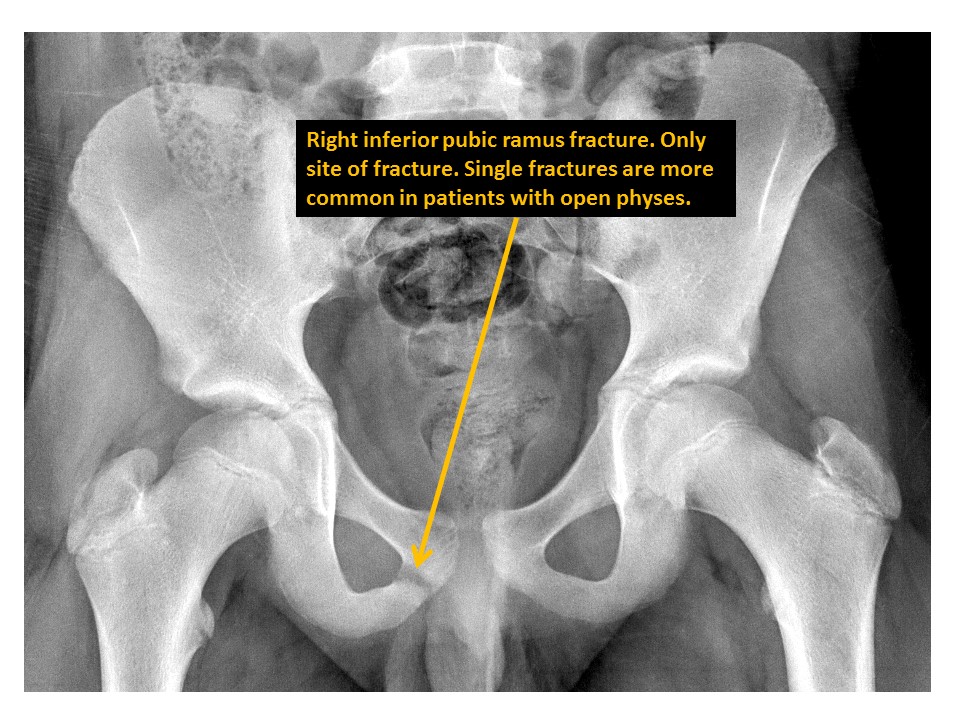

There is a pubic ramus fracture. [Yes/No]